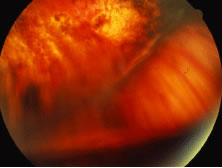

Others and we have reported a high incidence (up to 22%) of rhegmatogenous retinal detachment in association with ganciclovir treatment for CMV retinitis.115 The presence of chronic inflammation in these eyes may be important in the pathogenesis of proliferative vitreoretinopathy and retinal detachment (Figs. 24, 25, and 26). Inflammatory products and cells may contribute to contraction of the vitreous gel by stimulating migration of contractile cells or by metaplasia of macrophages into contractile elements that contribute to posterior vitreous detachment.105

Fig. 24. Rhegmatogenous retinal detachment associated with cytomegalovirus (CMV) retinitis. The retina is extremely thin and filled with atrophic breaks; these are best seen in the superior aspect of the illustration.

Fig. 25. Proliferative vitreoretinopathy (PVR) manifest by star fold is seen in a patient with rhegmatogenous retinal detachment associated with healed cytomegalovirus retinitis. PVR is very unusual in cytomegalovirus (CMV) retinitis, however, it may occur in associated with immune recovery uveitis.

Fig. 26. A case of rhegmatogenous retinal detachment associated with cytomegalovirus (CMV) treated successfully with peripheral retinal laser, vitrectomy, and buckling. Note that the silicone oil does not provide inferior tamponade. There is a shallow detachment between the posterior edge of the scleral buckle and the area of peripheral scatter laser that has prevented progressive retinal detachment.